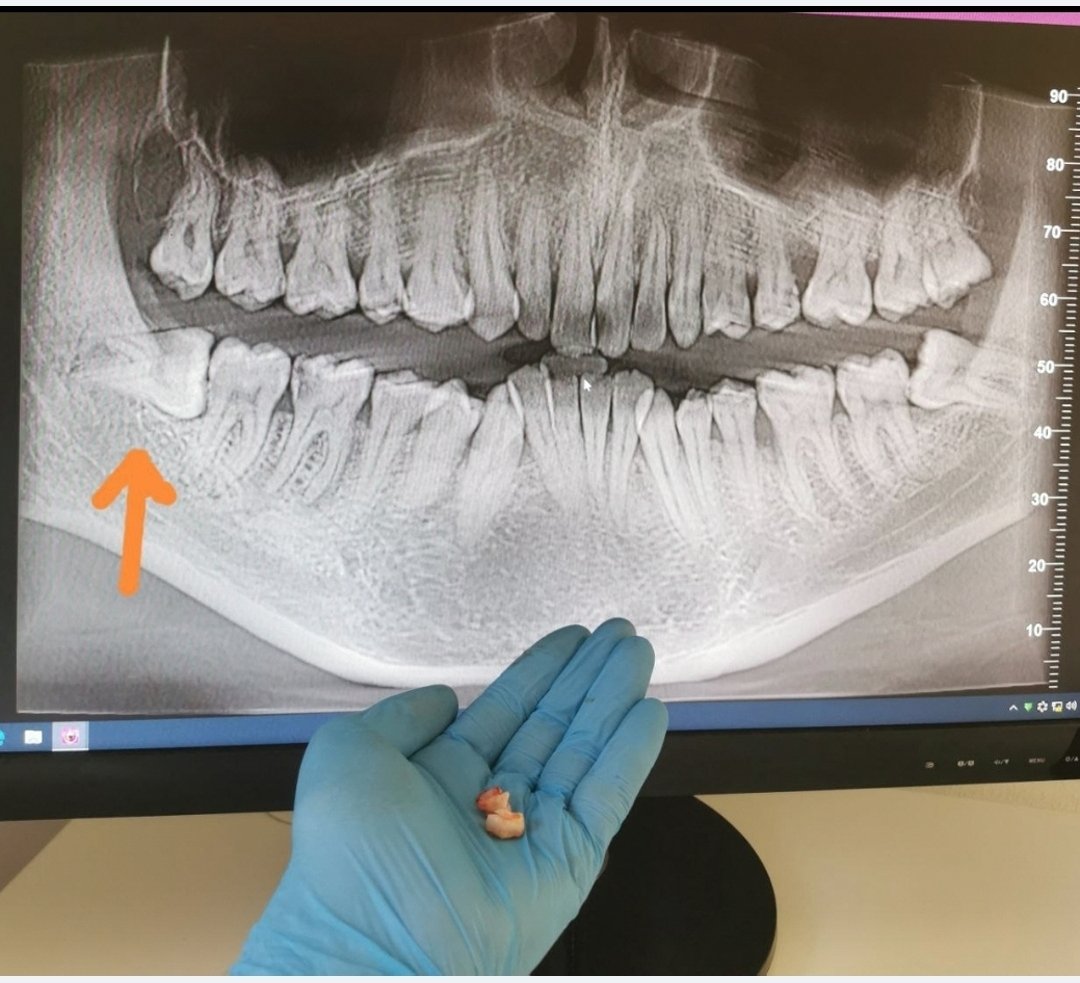

Zubná chirurgia – stomatochirurgia

Extrakcia/vytrhovanie zubov a stomatochirurgické zákroky.

Fotografie